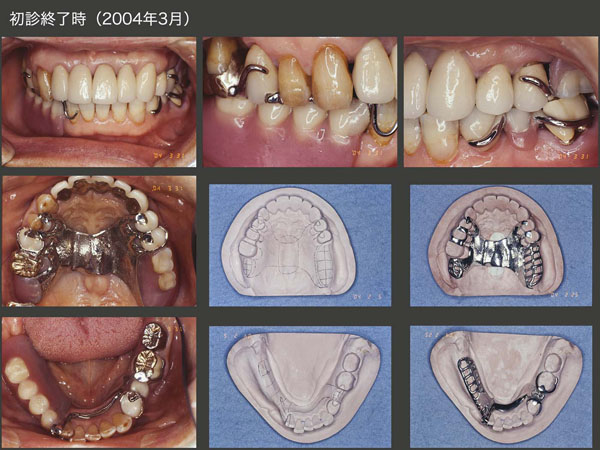

2017年11月,初診から15年2ヵ月,初診終了から13年8ヵ月後の状態.この間,初診時に抜歯した保存不可能な右下3を除き,11年に右上6,および17年に左下6の遠心根を失っただけであることから,経過は良好と言える.しかし,12年8月の右上5のデンタルX線写真からみてとれるように,支持歯槽骨がほとんど存在しない状態で,17年まで保っているということは,言い換えれば右側ではほとんど咀嚼していないことになる.11年に行った人工歯排列位置の改変は効果がなかったように思われる.なお,左上1,2の予後が心配であったが,特に問題は生じていない.

義歯装着時の状態.初診終了から約14年経っても,これほどレストの適合に変化がみられない症例はほとんど経験していない.このことは,咬合力が弱いことを意味するのか?もしくは,義歯ではまったく咀嚼せず,左側の咬合支持歯のみで咀嚼しているのかもしれない.